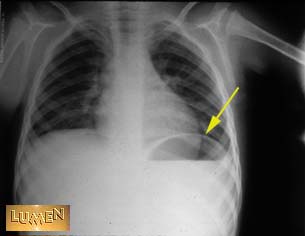

Question: Identify line.

Left diaphragm.